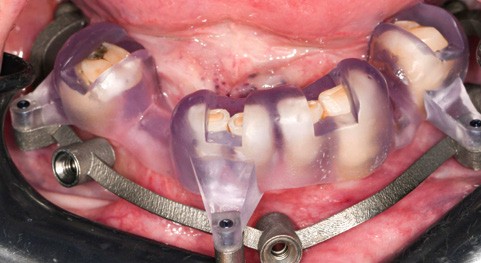

Un premier étage, appelé guide base, est fixé sur le maxillaire à implanter et servira de socle pour les étages supérieurs à empiler (fig. 2). Il doit être aussi rigide que stable pour supporter les contraintes pendant toute la durée de l’intervention : celles du forage implantaire comme celles des poses et déposes des étages supérieurs. Son bon positionnement est donc crucial car il déterminera celui des autres étages. Il peut également servir de repère en fin de procédure, tel un guide de scannage, pour réaliser une empreinte optique (fig. 3). Les appuis sont aussi divers qu’avec un guide statique conventionnel :

- appui dentaire : il est le plus fiable car son positionnement est permis grâce à des points fixes (fig. 4). Il reste bien sûr dépendant de la précision de l’alignement entre le STL de l’empreinte optique et le DICOM de l’examen CBCT ;